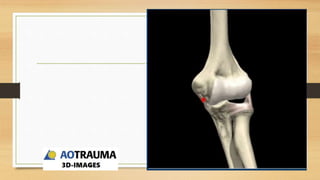

MEHNE Y JUPITER PARA

FRACTURAS ARTICULARES

EN H Y LAMBDA TIENE

MAYOR RIESGO DE NECROSIS

AVASCULAR